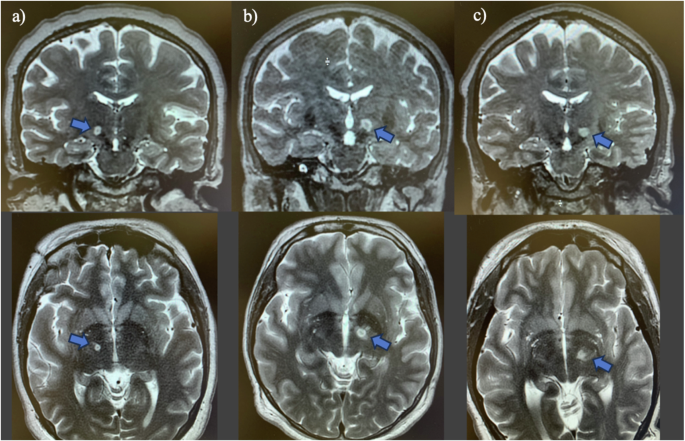

Figure 1. Magnetic Resonance Images in Two Patients Immediately After MRgFUS Subthalamotomy. Coronal (A) and axial (B) T2-weighted views obtained immediately after the procedure. The site of the lesion is recognizable by a heterogeneous central area corresponding to tissue necrosis, which is typically hypointense (black) on T2-weighted images. This zone is delimited by a rim of perilesional cytotoxic edema, hyperintense (white) on T2-weighted images. An additional hyperintense area on T2-weighted imaging corresponds to edema spreading within the white matter surrounding the subthalamic nucleus.